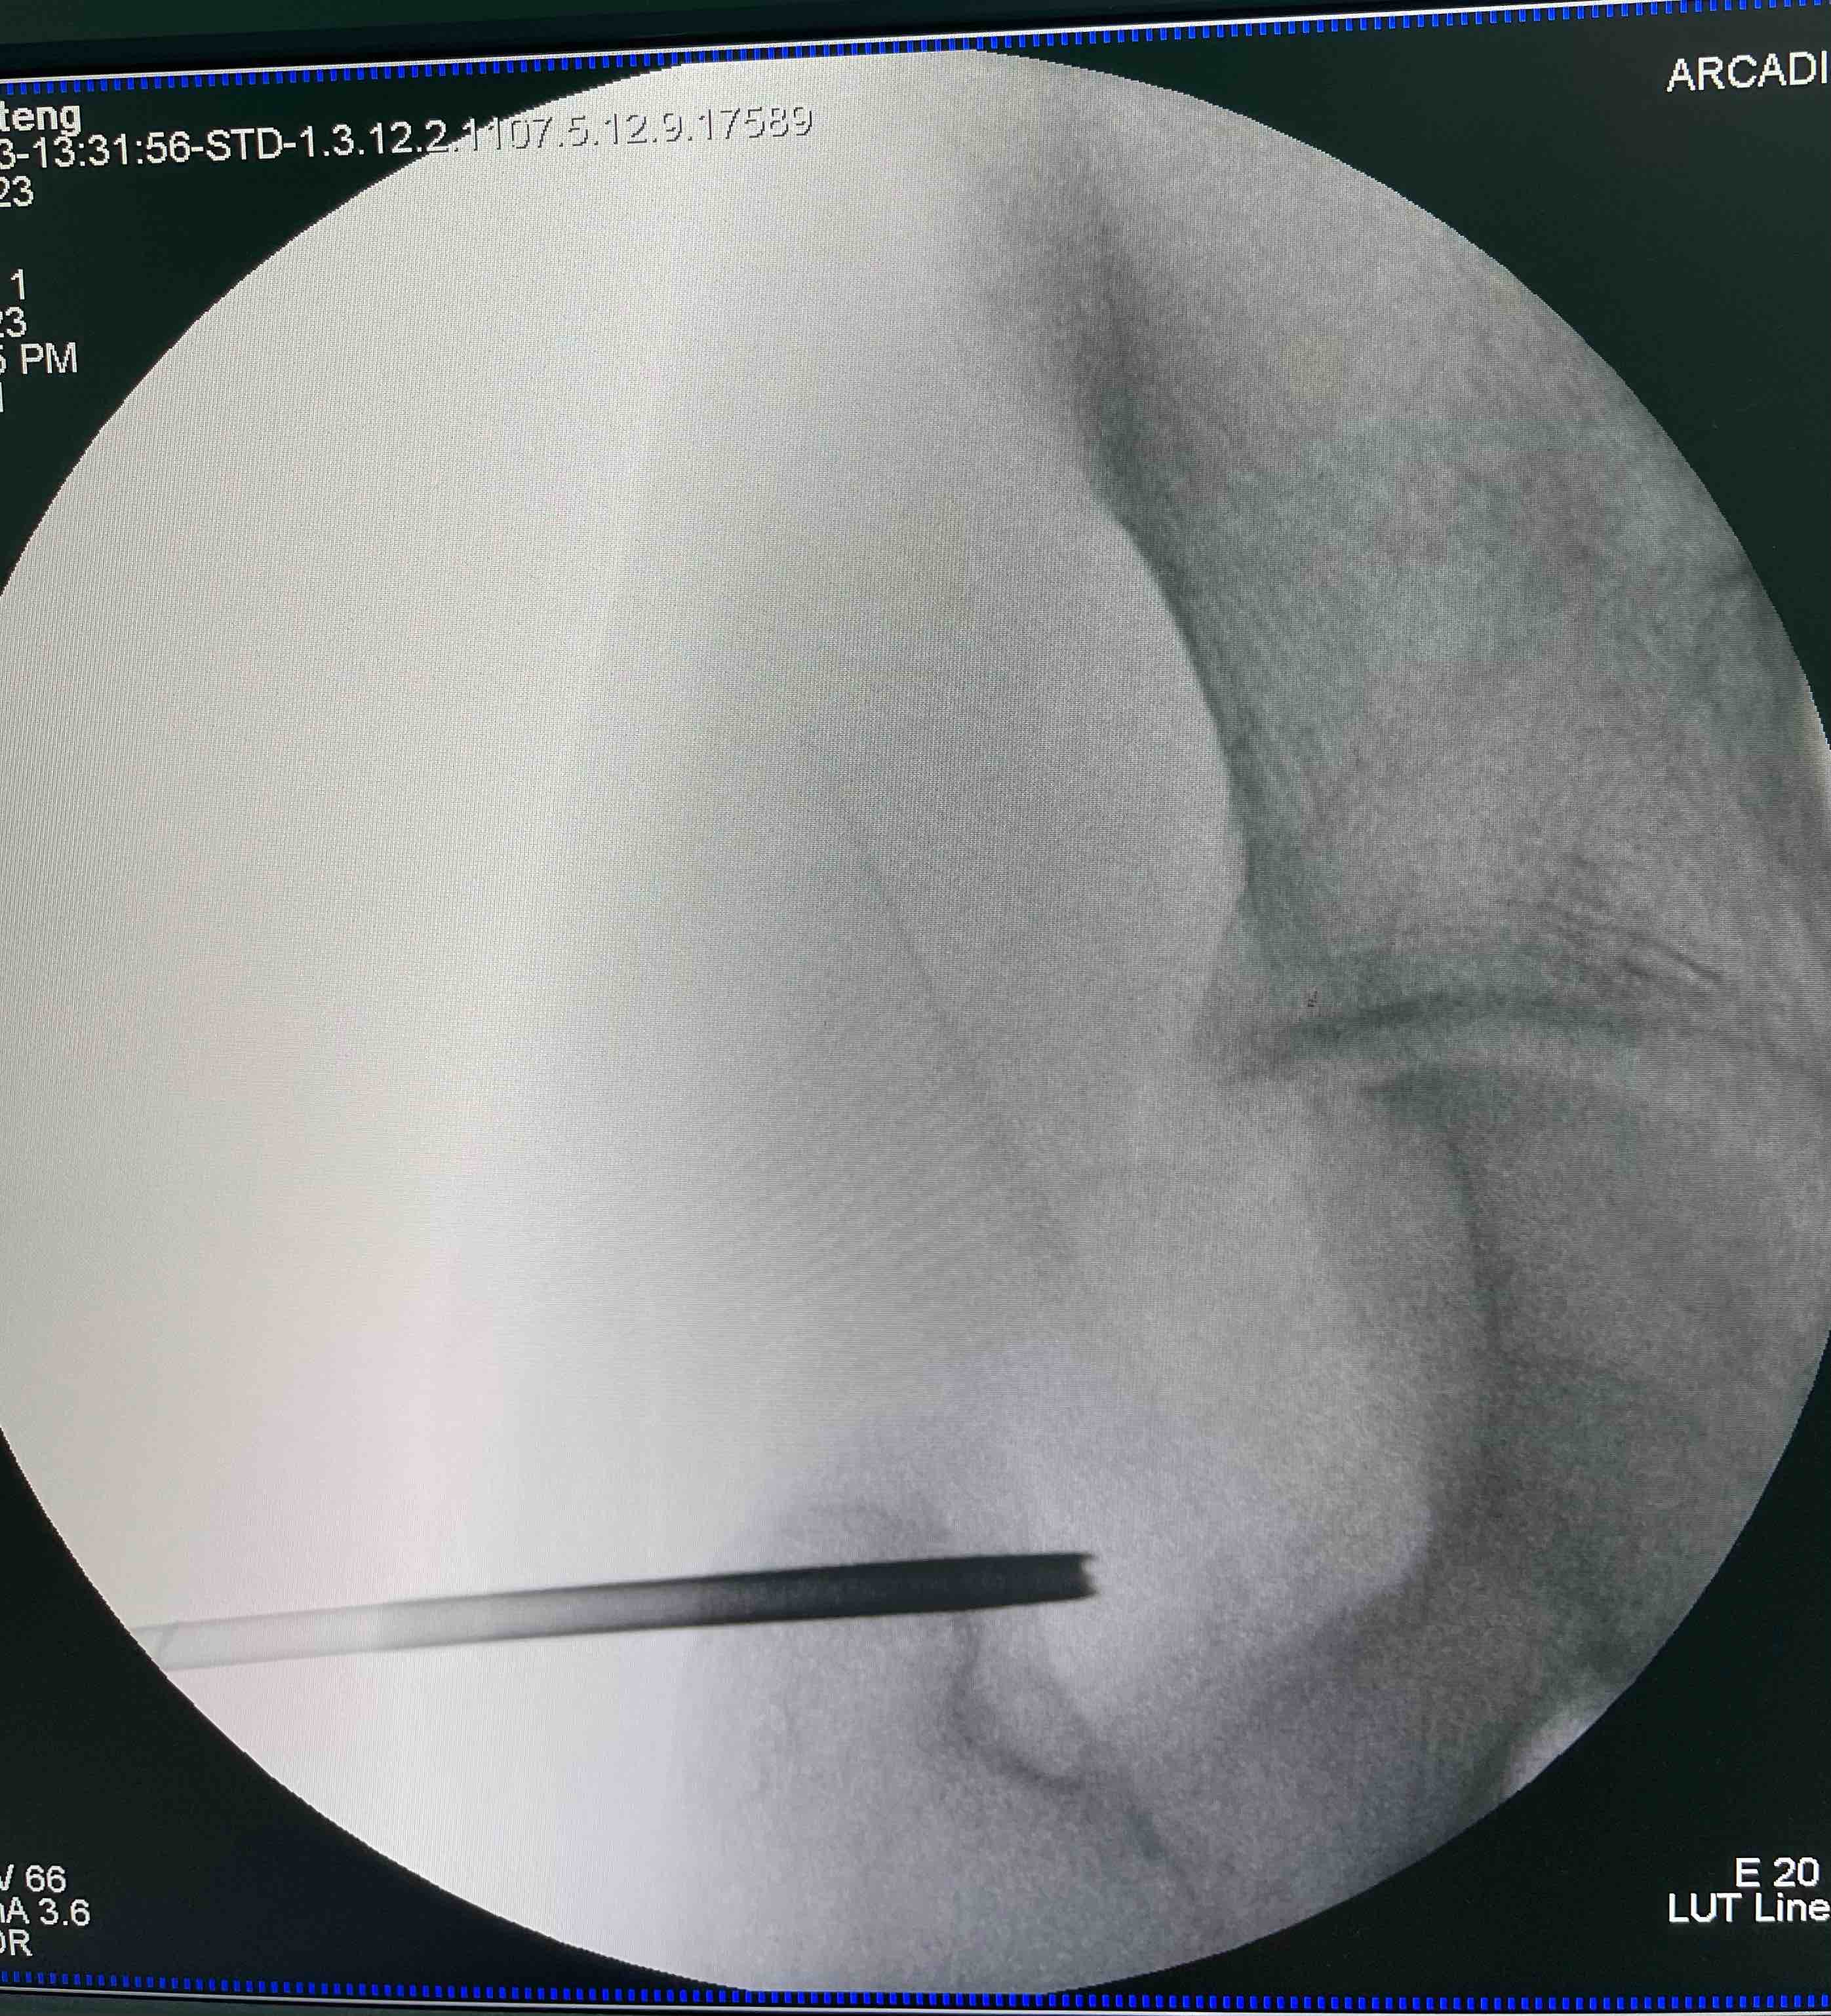

经典的活检方式,切开活检,但因其与穿刺活检相比并发症较多,如出血、感染、肿瘤污染周围组织等。因此,临床更常见的为穿刺活检。

针吸穿刺在良恶性的确诊率方面达到84-97%,但是在明确病理学诊断和分级方面为81%。明确良恶性、诊断和分级,有助于医生和患者选择合适的手术及诊疗方案。而最终的诊断依然是临床+影像+病理三结合。